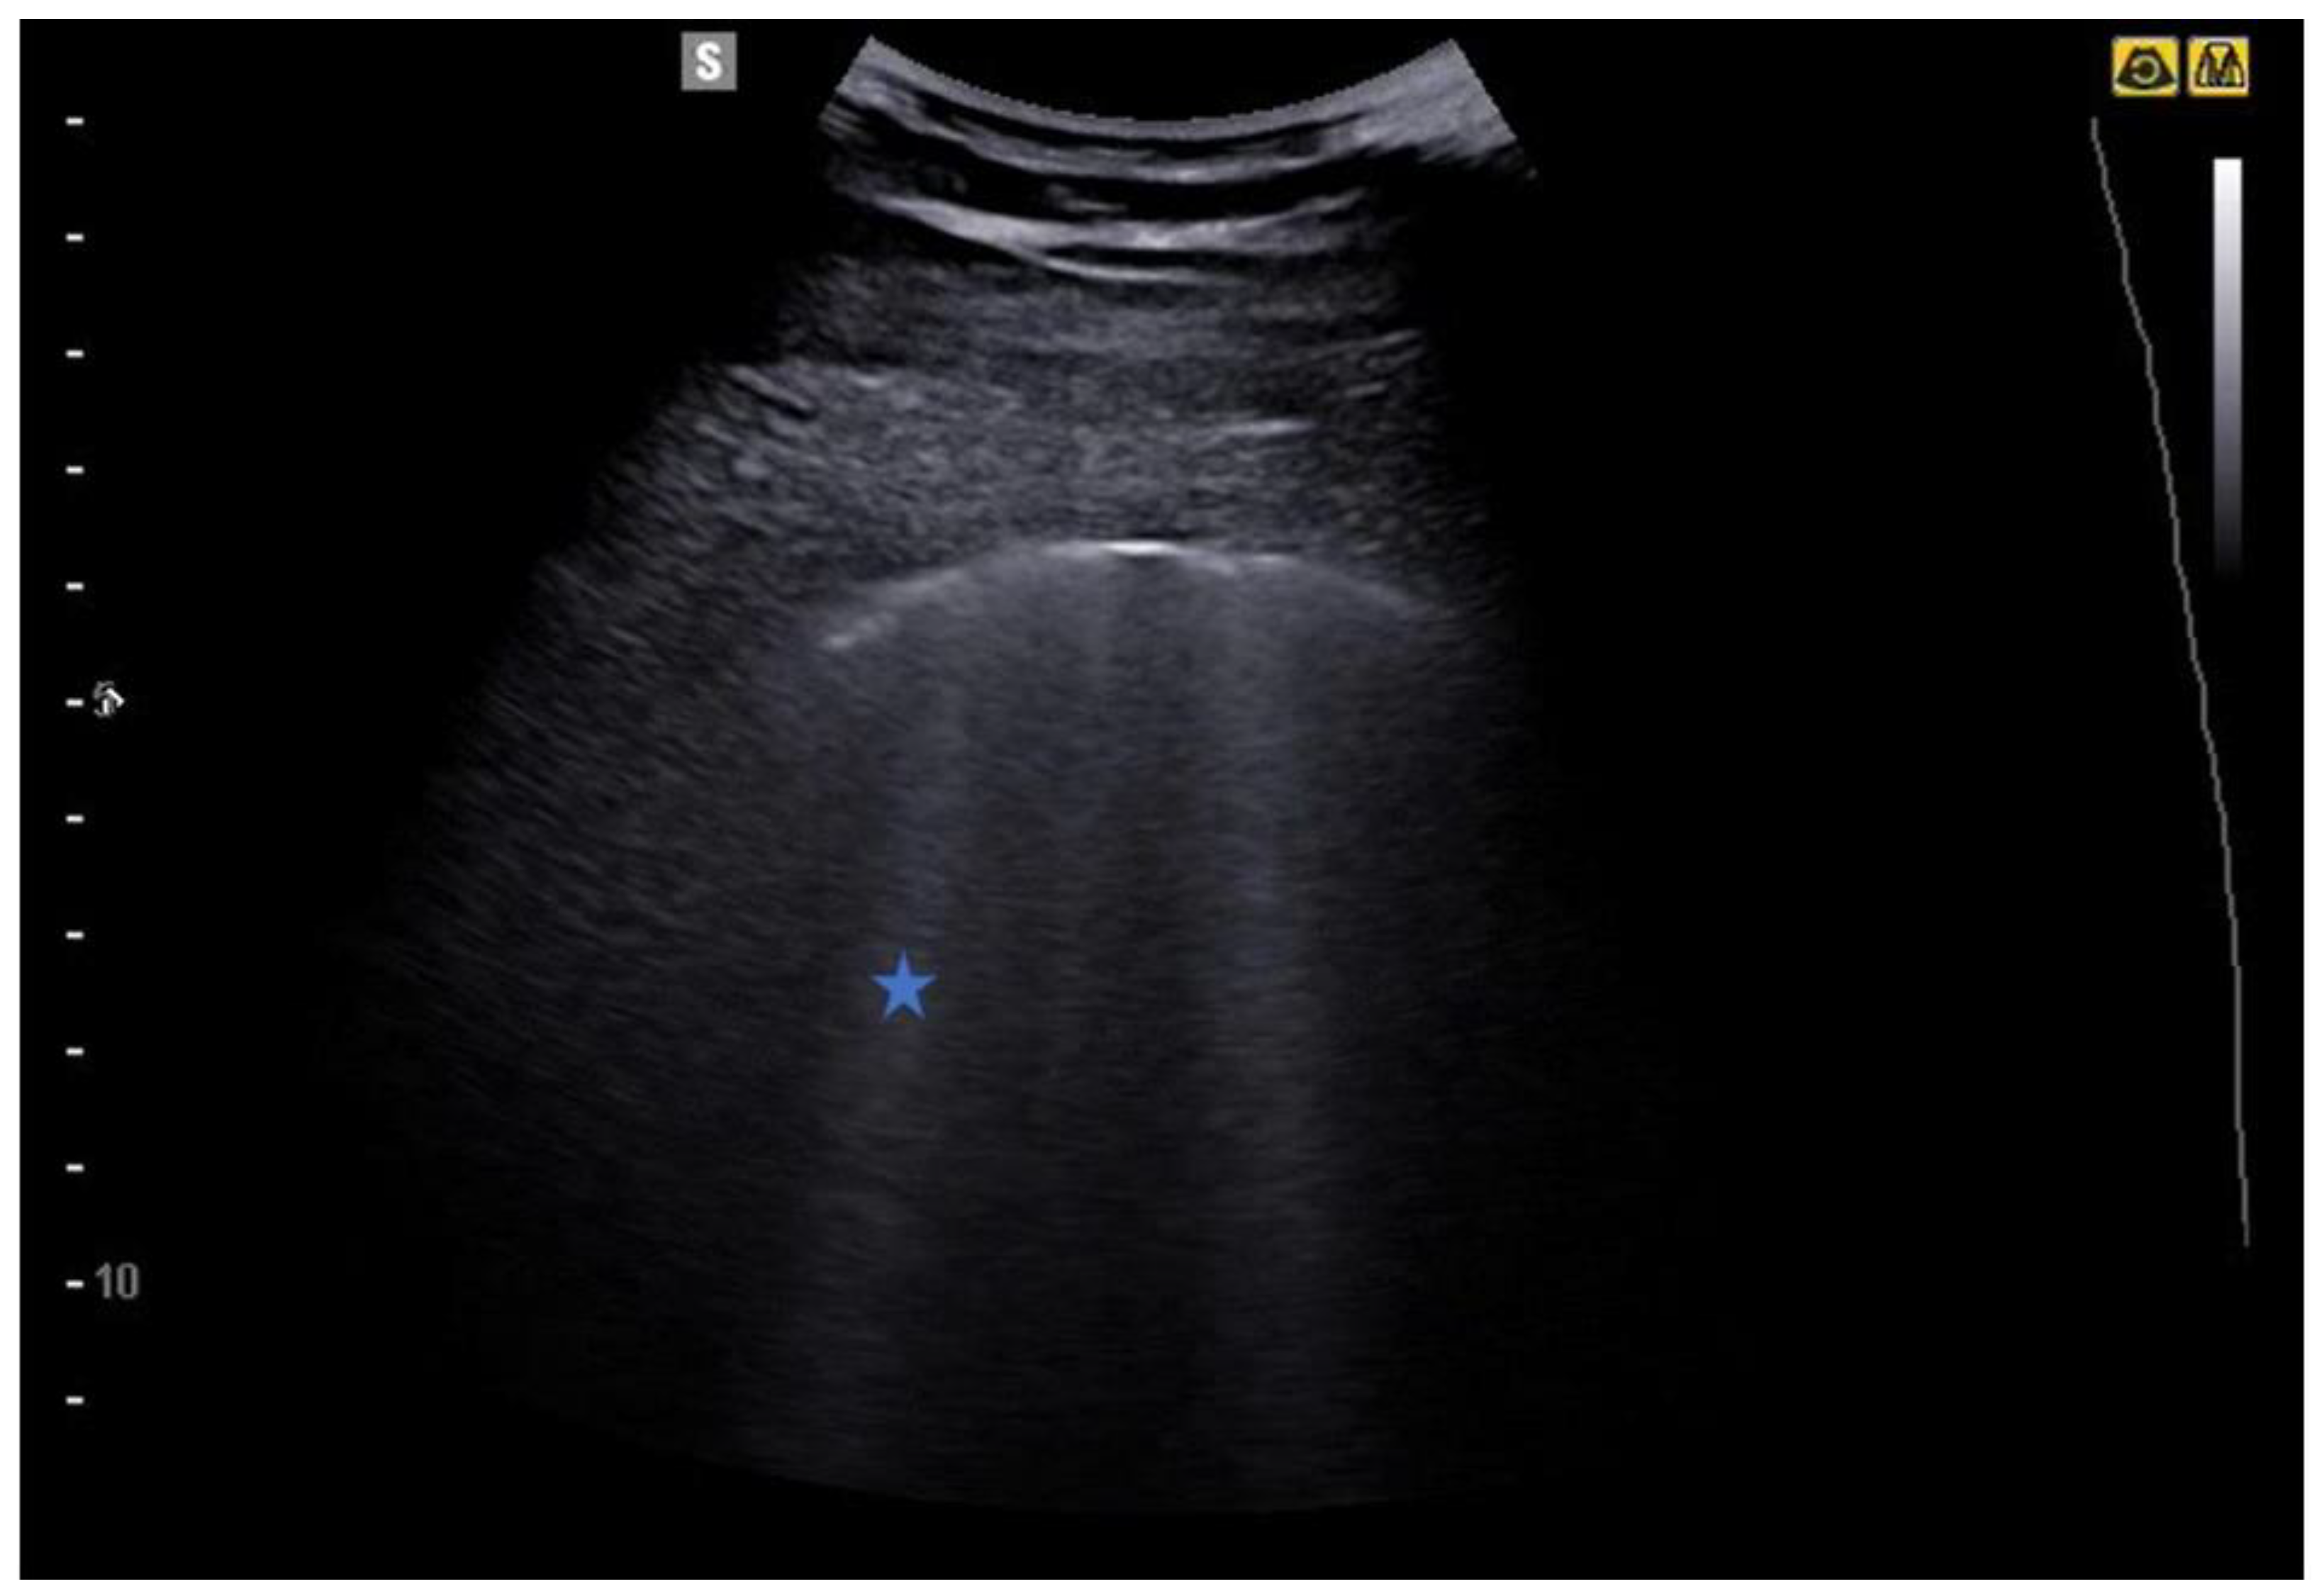

5.1. Interstitial Syndrome

5. From the B-Lines to the Pathological Lung